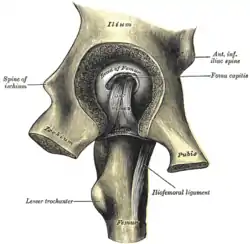

The obturator externus. Left hip-joint, opened by removing the floor of the acetabulum from within the pelvis.

Left hip-joint, opened by removing the floor of the acetabulum from within the pelvis. Pubis